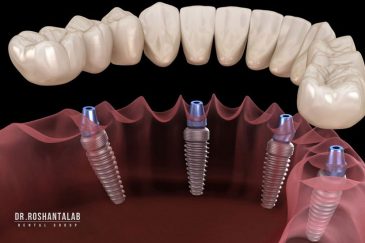

🔸کاشت ایمپلنت فلپ لس یا بدون جراحی و بدون بخیه زیر سه دقیقه

🔸 کاشت دندان یک روزه ( کشیدن و کاشت همزمان )

تجربه کاشت دندان دیجیتال و بدون درد در ۳ دقیقه! استفاده از برترین برندها زیر نظر جراح، با هزینه مناسب و خدمات کامل از کاشت دندان تا روکشارتودنسی دندان